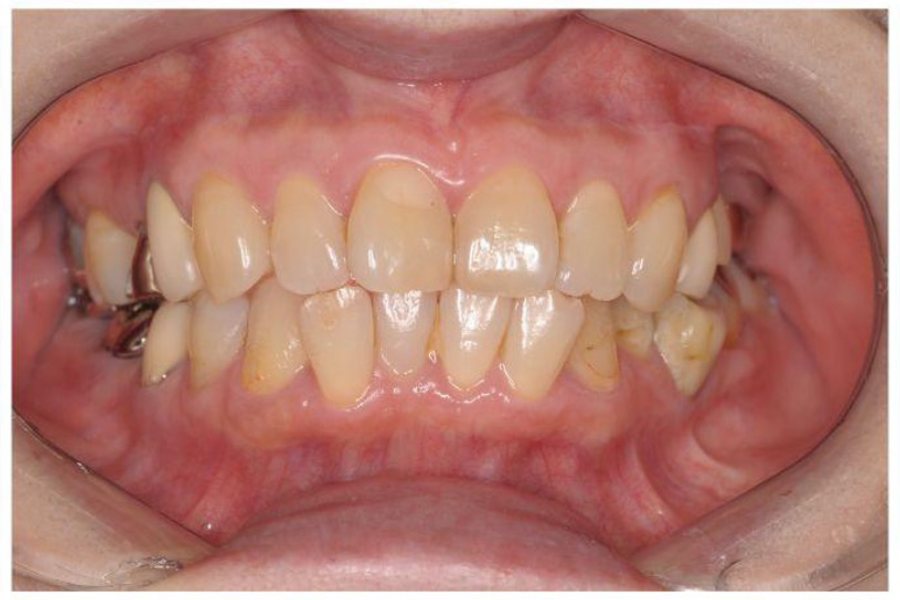

治療前